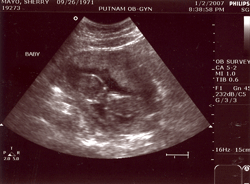

I'm really happy that I'm pregnant and that we're having a baby. It is amazing how connected I am to peaches already. That said I'm not that into the process. The